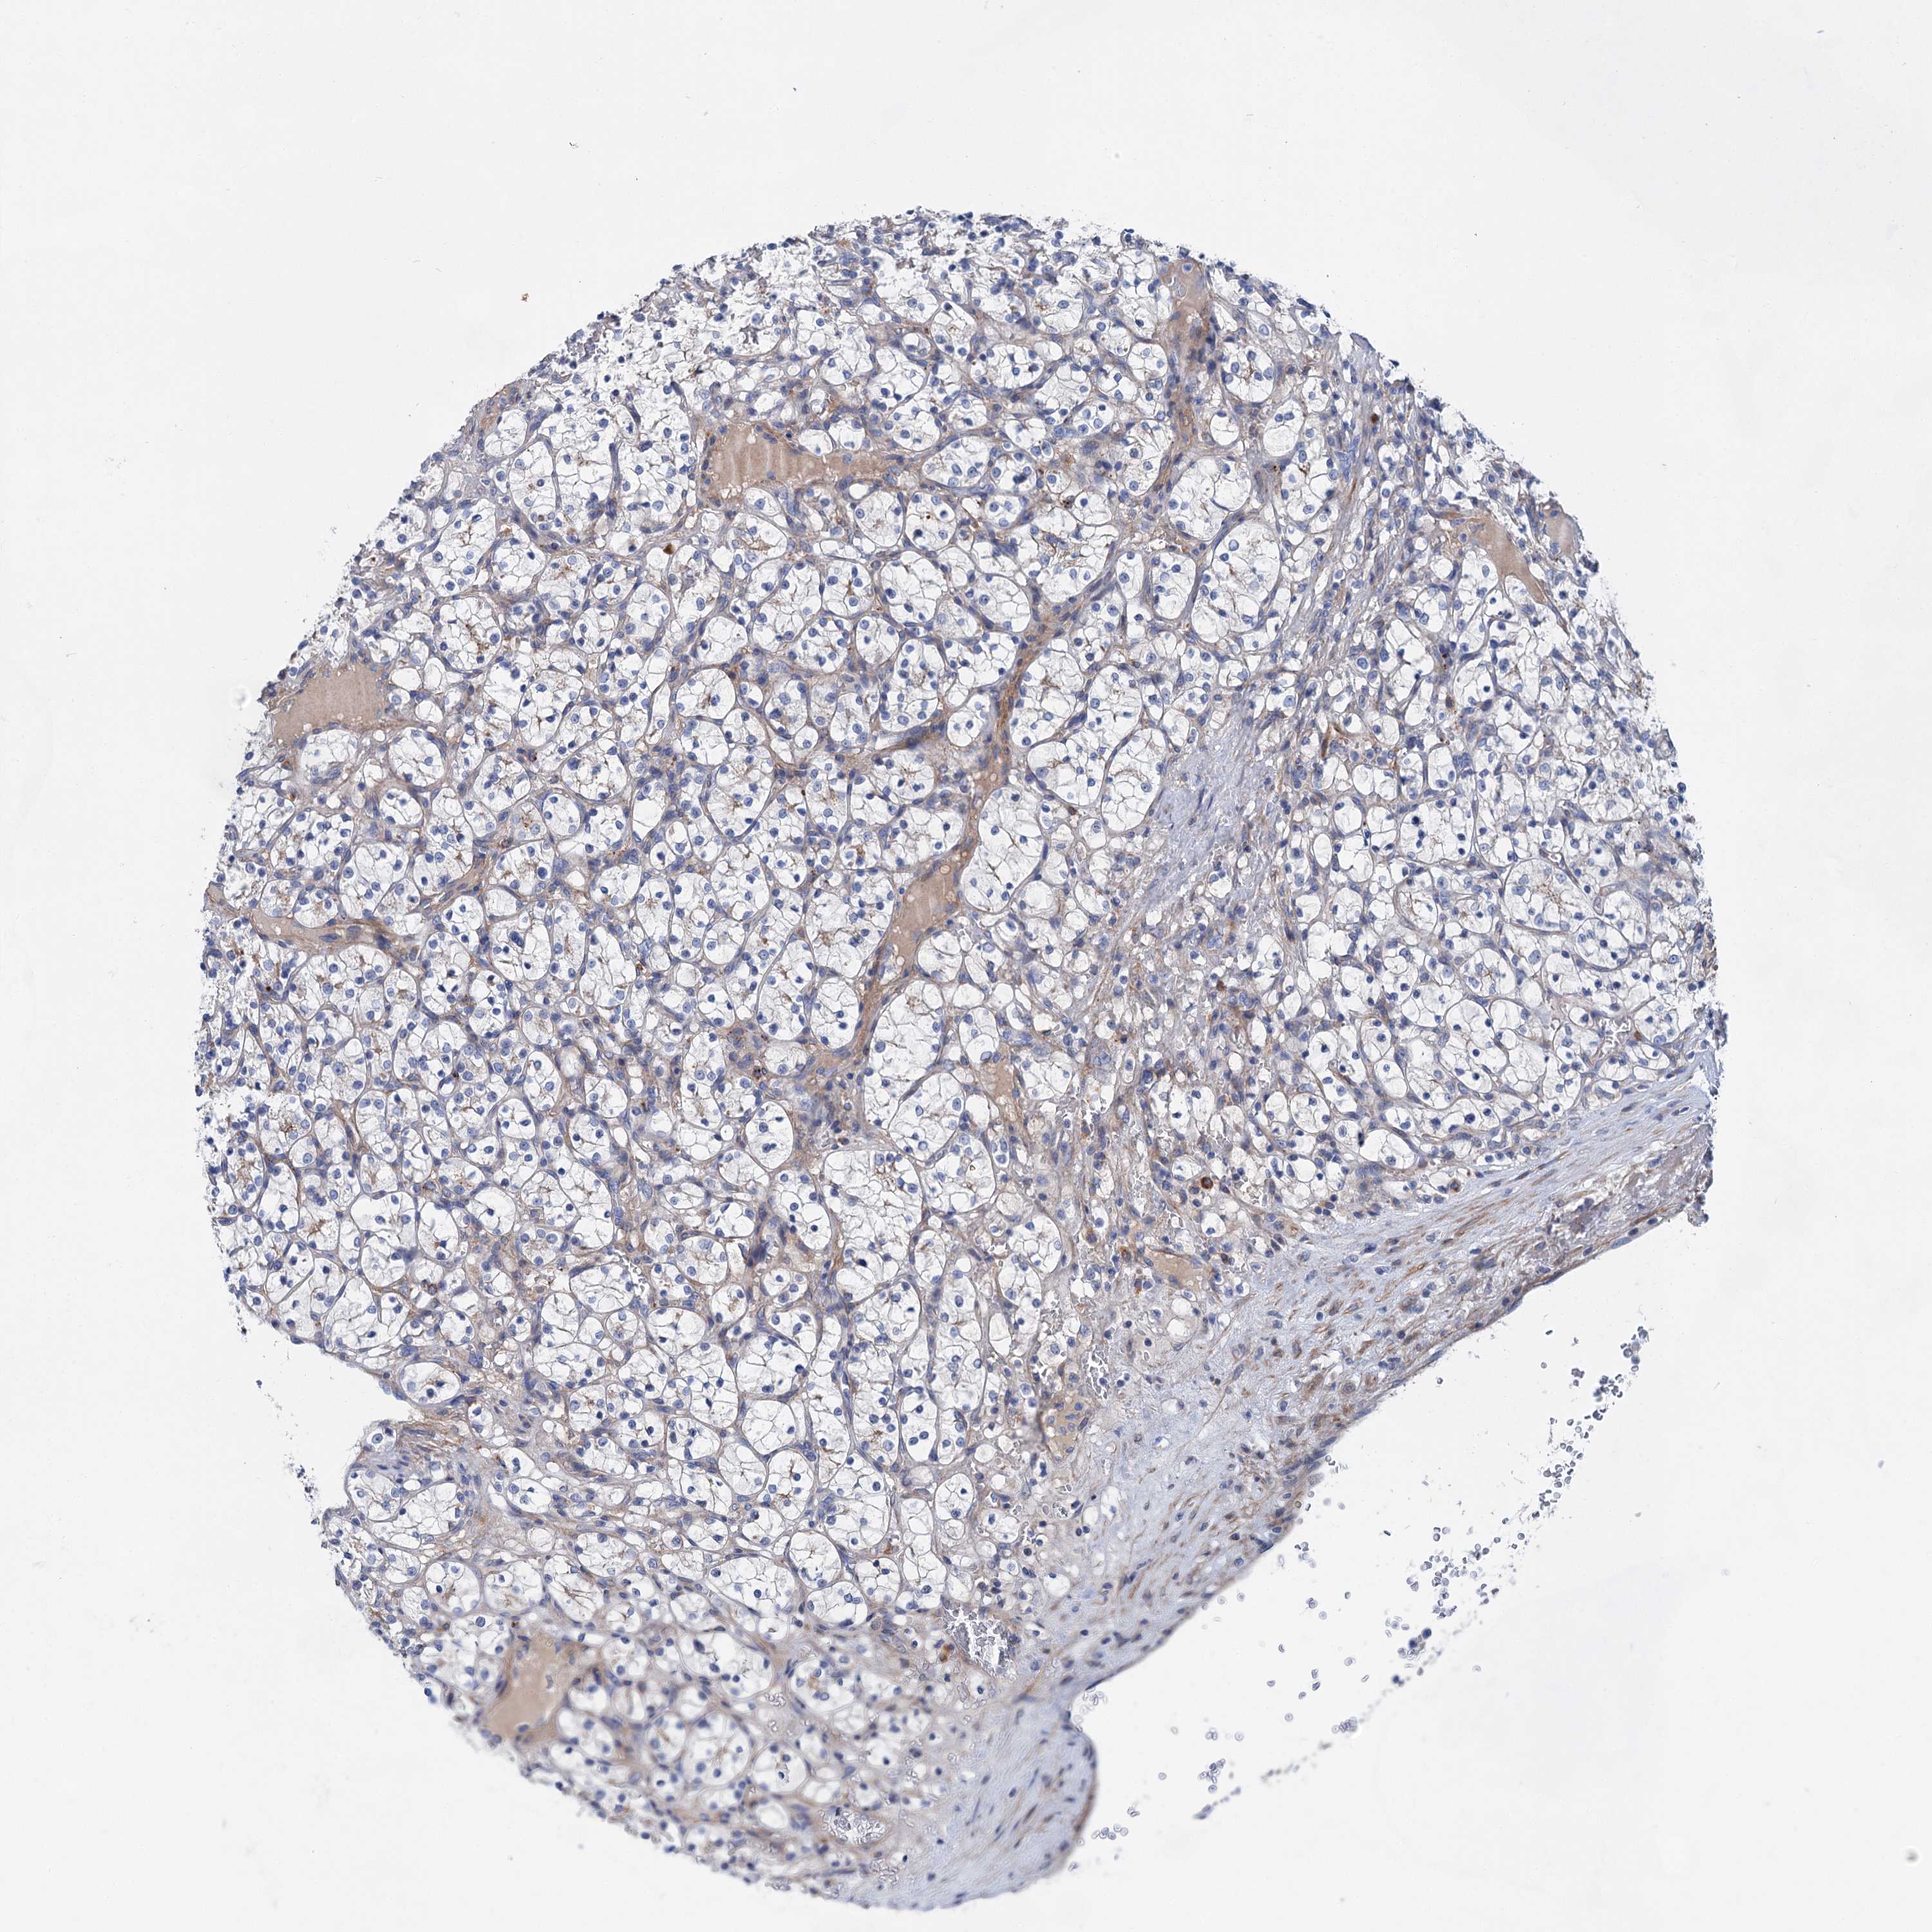

KIDNEY RENAL CLEAR CELL CARCINOMA (VALIDATION) - Interactive survival scatter ploti

GPR155 is not prognostic in Kidney Renal Clear Cell Carcinoma (validation)

Best expression cut offi

: 10.21

TCGA RNA samplesi

Average pTPM 8.7

Number of samples 100